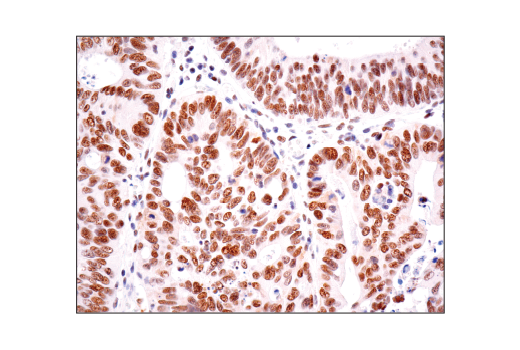

Immunohistochemical analysis of paraffin-embedded human colon carcinoma using HAUSP (D17C6) XP® Rabbit mAb.

Immunohistochemistry Image 1: HAUSP (D17C6) Rabbit Monoclonal Antibody